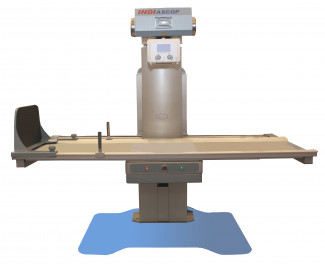

КРД "INDIascop" на три робочих місця з технологією томосинтезу, вироблені Заводом рентгенівського обладнання «Квант», протягом року успішно експлуатуються в лікувальних установах м. Києва та м. Харкова.

Сучасна конструкція КРД "INDIascop" дозволяє виконати серію низькодозових експозицій, під час якої рентгенівська трубка рухається щодо досліджуваного об'єкта по дузі, а приймаючий пристрій змінює своє положення в протилежному напрямку. Завдяки даній технології можливо проводити оцінку щільності кісткових структур, більш ефективно виявити порожнинні освіти довгих трубчастих кісток, а також діагностувати новоутворення в легенях, які при звичайному обстеженні можуть бути приховані кістковою тканиною і залишитися непоміченими.